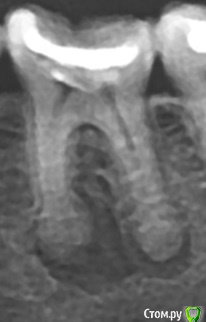

miep Опубликовано 13 декабря, 2017 Поделиться Опубликовано 13 декабря, 2017 При лечении кистогранулемы остался инструмент в канале. насколько опасно это? какие последствия могут быть?достать даже под микроскопом не получилось (хотя особо то и не пытались, так 15 мин покопались, испугались перфорации и оставили) . Можно ли будет под коронку этот зуб?Через сколько можно коронку ставить? Всегда считала что такие зубы лучше оставить так -мало ли вдруг рецедив...Врач изначально сказал удалять. я уломала полечить... и вот удивительные результаты....) Ссылка на комментарий

miep Опубликовано 13 декабря, 2017 Автор Поделиться Опубликовано 13 декабря, 2017 Динамика хорошая, сколько прошло после лечения?начали лечение 8 августа. снимок сегодняшний последний который. еще кальций на месяц положили. Дальше он говорит постоянно хочет запломбировать каналы, если не будет ухудшений. это в середине января должно быть Ссылка на комментарий

DmitrySH Опубликовано 23 декабря, 2017 Поделиться Опубликовано 23 декабря, 2017 Так и никто не может сказать по снммку что с инструментом делать то ?)Ничего не делать, запломбировать как есть и наблюдать. 2 Ссылка на комментарий